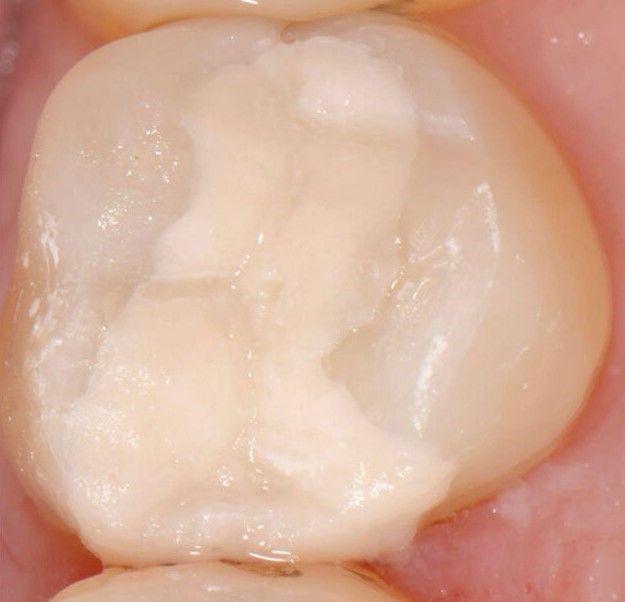

Keramikfüllungen (auch Kompositfüllungen genannt) bestehen zu ca. 80% aus keramischen Füllkörpern, die in einer Kunststoffmatrix eingelagert sind und zunächst eine Marzipan-ähnliche Konsistenz haben. Nachdem der Zahn mit einer speziellen Klebetechnik vorbehandelt wurde, wird dieses Material in kleinen Portionen eingebracht und diese Portionen dann separat lichtgehärtet. Durch die Lichthärtung verbinden sich die Elemente der Kunststoffmatrix zu einem stabilen Netzwerk, in dem die hochfesten feinen Keramikpartikel eingelagert sind. Diese Technik ist deutlich zeitaufwändiger und techniksensitiver als die einer Zementfüllung. Die aus der Verbindung von Material, Klebetechnik und Lichthärtung hervorgegangenen Füllungen zeichnen sich durch folgende Vorteile aus:

- Sie sind hoch ästhetisch, da individuell zahnfarben und transluzent.

- Sie sind in sich sehr stabil und abriebfest und bewahren ihre Form jahrelang.

- Sie sind deutlich bruchfester als Zementfüllungen, es können auch größere Defekte versorgt werden.

- Sie können die verbliebene Zahnsubstanz durch die Verklebung stabilisieren.

- Sie schonen die eigene Zahnsubstanz, da sie seltener als Zementfüllungen erneuert werden müssen und oft die Anfertigung einer Teilkrone oder Krone überflüssig machen.